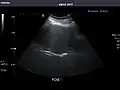

Left kidney